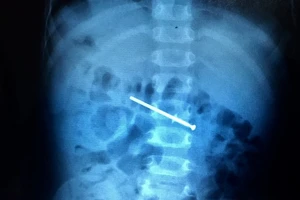

Được bố cho chơi, bé trai 18 tháng tuổi nuốt luôn... cây đinh